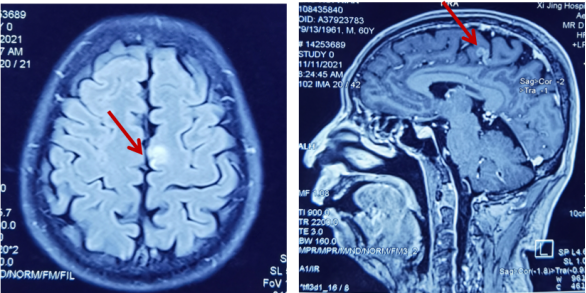

骨骼是肺癌常见的转移部位之一,骨转移癌会导致骨痛、病理性骨折、脊髓压迫、高钙血症等骨相关事件(SRE),其中,骨痛是骨转移癌最常见的临床症状,严重影响患者生活质量。地舒单抗,首个落户中国的核因子κB受体活化因子配体(RANKL)抑制剂,为防治SRE提供新的选择。本次分享地舒单抗治疗以骨痛为主要症状的EGFR突变晚期肺癌骨转移患者案例,希望为SRE的防治带来启迪与思考。 白引苗 空军军医大学第一附属医院肿瘤科 主治医师 中国抗癌协会肿瘤标志物专业委员会 委员 陕西省抗癌协会肿瘤化疗专业委员会 委员 陕西省抗癌协会肿瘤热疗专业委员会 委员 陕西省抗癌协会多原发和不明原发肿瘤专业委员会委员 擅长食管癌、胃癌、结直肠癌、胰腺癌等消化系统、肺癌及妇科常见恶性肿瘤的化疗、靶向治疗及免疫治疗等内科治疗。参译著作1部,参编著作1部,发表核心期刊论文多篇。 一般资料:患者男性,60岁 主诉:右侧肩部疼痛 现病史:2019年8月因右侧肩部疼痛于外院就诊,疼痛NRS评分3-4分,口服依托考昔症状可缓解 个人史:否认吸烟、饮酒嗜好 家族史:1兄因“胃癌”病故 辅助检查: 外院右肱骨MRI:右侧肱骨骨转移可能,合并肱骨中段骨质破坏。 外院胸部CT(图1):右肺下叶周围型肺癌,可疑肺门、纵隔淋巴结转移,T3/4/8椎体骨转移。 图1 胸部CT(箭头指示右肺下叶病变) PET/CT(18F-FDG)(图2-3):右肺下叶基底段软组织病变(3.7 cm×4.6 cm×4.7 cm,SUV max 6.9,平均值6),浅分叶、边缘见毛刺;右侧锁骨上下区、隆突区稍大淋巴结(长径0.6 cm-1.4 cm,SUV max 2.5-4.6,平均值2.2-3.2),考虑转移;脊柱多个椎体及附件、双侧多个肋骨、骨盆多处、双侧股骨上段多发骨质破坏(SUV max 2.0-5.7,平均值1.7-3.9),考虑转移。 图2 PET/CT提示右肺下叶基底段病变及右锁骨上下区、隆突区稍大淋巴结 图3 PET/CT提示多发骨质破坏 患者接受CT引导下经皮右肺病变穿刺活检,病理(图4):光镜见异型细胞呈条索状、腺管样排列,细胞核大、深染,异型性明显;免疫组化:AE1/AE3(+),CK5/6(-),CK7(+),CK8/18(+),P40(-),P63(-), Napsin A(+),ALK(D5F3 Ventana IHC)(-),TTF-1(+),Ki67 30%,支持腺癌。 肿瘤标志物:CYFRA21-1 5.8 ng/ml(参考值:0-3.3 ng/ml),CEA、SCC、NSE正常。 基因检测:EGFR基因19del突变。KRAS、NRAS、PIK3CA、BRAF、HER-2基因未检测到突变;ALK、ROS1、RET基因未检测到融合。 诊断:肺恶性肿瘤(右侧,腺癌,cT2N3M1,IV期,EGFR 19del);骨继发恶性肿瘤(多发);淋巴结继发恶性肿瘤(多发)。 双管齐下、并驾齐驱——抗癌治疗与唑来膦酸齐头并进 2019年9月患者接受奥希替尼80 mg/日一线治疗,同时接受唑来膦酸4 mg/月改善SRE。1个月后复查CT示右肺病变缩小40%(4.7 cm至2.8 cm);肿瘤标志物CYFRA21-1由5.8 ng/ml降至3.67 ng/ml;右肩部疼痛消失(停用止痛药)。 2020年3月复查胸部CT(图5)提示:肺部病变进展(增大39.3%,2.8 cm至3.9 cm);肿瘤标志物CYFRA21-1缓慢升高至7.05 ng/ml。考虑局部进展,在奥希替尼基础上联合培美曲塞+卡铂治疗4个周期,后给予奥希替尼联合培美曲塞维持治疗14个周期。 图5 胸部CT(2020年3月,箭头指示右肺病变) 最佳疗效:右肺病变缩小51.3%(至1.9 cm)(图6);肿瘤标志物CYFRA21-1由7.05 ng/ml降至1.4 ng/ml。 图6 二线治疗前(左图)后(右图)胸部CT比较(箭头指示右肺病变) 2021年4月患者感背部钝痛,NRS评分5-6分,口服氨酚羟考酮330 mg/8 h,症状可缓解。骨扫描(ECT)与单光子发射计算机断层扫描(SPECT)/CT提示骨转移加重。停用唑来膦酸,使用地舒单抗120 mg/月,疼痛有缓解。 2021年9月复查胸部CT示右肺下叶病变进展(1.9 cm至3.4 cm)。肿瘤标志物CYFRA21-1由10.73 ng/ml升至13 ng/ml。患者感背部疼痛加重,NRS 评分5-6分。行CT引导下右肺病变再次穿刺活检,病理提示肺腺癌,PD-L1(SP263)(TPS=80%),Ki67 85%。基因检测:EGFR 19del,KRAS、NRAS、PIK3CA、BRAF、HER-2基因及MET exon14无突变;ALK、ROS1、RET基因无融合。 遂调整为白蛋白结合型紫杉醇化疗2周期,奥希替尼和地舒单抗方案同前,患者背部疼痛消失。 2021年11月复查PET/CT:原右肺下叶基底段团块状软组织病变较初诊缩小(1.8 cm×1.6 cm×3.8 cm);原右侧锁骨区多发淋巴结消失;原隆突区稍大淋巴结缩小(0.5 cm);原脊柱多个椎体及附件、双侧多个肋骨、骨盆多处、双侧股骨上段多发骨质破坏,病变密度增高,考虑治疗有效,部分仍有代谢活跃;右侧颞叶片状低密度影。查头颅MRI(图7):左侧额叶大脑镰旁(0.7 cm×0.7 cm×1 cm)、右侧颞叶脑皮质表面(1.2 cm×1.3 cm×0.8 cm)异常强化灶,考虑转移。 图7 头颅MRI(箭头指示颅内病变) 经MDT讨论,建议脑部病变随诊观察。鉴于出现脑转移癌,调整为伏美替尼80 mg/日口服、白蛋白结合型紫杉醇静脉化疗;继续予地舒单抗。 患者治疗期间碱性磷酸酶(ALP)水平变化如图8所示。 图8 血清碱性磷酸酶变化情况 患者于2019年8月因右侧肩部疼痛就诊,确诊右肺腺癌Ⅳ期伴多发骨转移及淋巴结转移,EGFR 19del突变。一线治疗:奥希替尼(80 mg/日)+骨改良药物唑来膦酸(4 mg/月),最佳疗效:右肺肿瘤PR(缩小40%)、疼痛症状缓解,一线治疗PFS时间7个月。2020年3月,肺部病灶进展,予奥希替尼+培美曲塞联合卡铂4周期,后培美曲塞维持治疗14周期,继续予唑来膦酸治疗;2021年4月背部钝痛加重,骨扫描提示骨病变进展,遂停用唑来膦酸,予地舒单抗120 mg/月治疗至2021年9月,二线PFS 18个月。后因肺部病灶进展,三线治疗给予奥希替尼+白蛋白结合型紫杉醇及地舒单抗,患者背部疼痛症状消失。2021年11月头颅MRI示颅内转移,调整为予伏美替尼(80 mg/日)联合白蛋白结合型紫杉醇及地舒单抗治疗。 张红梅 西京医院肿瘤科主任 肿瘤学博士,硕士研究生导师 中国抗癌协会CMUP 副主委 中国临床肿瘤学会免疫专家委员会 常委 陕西省医学会肿瘤内科分会 副主委 主要从事肺癌等恶性肿瘤的内科治疗 我国肺癌发病率和死亡率均位于恶性肿瘤首位,20%-30%的晚期肺癌会发生骨转移[1],45%的肺癌骨转移患者会出现相关临床症状[2]。肺癌骨转移是患者生活质量降低、生存期缩短的独立危险因素,SRE如骨痛、病理性骨折、脊髓压迫等,不仅给患者带来生理上的痛苦与不便,也引发患者心理打击。因此,对于晚期肺癌骨转移患者,在控制原发疾病同时,亟需积极防治SRE,以达到提高患者生活质量、缓解生理心理痛苦、延长生存期的目的[3]。 本例肺癌同时性骨转移案例,以骨痛为首发症状,在奥希替尼治疗肺癌同时,首先予以唑来膦酸防治SRE,治疗初期患者症状一度改善。但随着疾病进展,唑来膦酸应用近20月后患者再次骨痛加重,影像学提示骨损害加重,对于这种骨病变进展、骨痛加重的临床问题,如何制定进一步治疗方案? 地舒单抗是IgG2型单克隆抗体,通过与RANKL结合,阻止其激活破骨细胞、破骨细胞前体和破骨细胞样巨细胞表面的核因子-κB受体活化因子(RANK),从而达到抑制肿瘤生长、减少骨破坏的目的。早在2010年,地舒单抗获得美国食品药品监督管理局(FDA)批准用于治疗实体瘤骨转移,目前已积累了丰富的证据临床研究和真实世界数据,显示其有效性和安全性。 地舒单抗与唑来膦酸治疗实体瘤骨转移和多发性骨髓瘤的Ⅲ期临床研究显示,地舒单抗可延缓首次出现SRE的时间(21.4个月 VS. 15.4个月)[4]。其中非小细胞肺癌患者,地舒单抗组较唑来膦酸组中位生存期(OS)延长1.5个月(9.5个月 VS. 8.0个月)[5]。安全性方面,地舒单抗也具有一定的优越性:与唑来膦酸组比较,地舒单抗组贫血、厌食症、肾脏不良事件、新发原发性恶性肿瘤的发生率较低[6]。地舒单抗通过网状内皮系统清除,不增加肾脏负担,对于肾功能不全的患者可作为首选。此外,作为皮下注射制剂,28天用药一次,无需住院完成,无疑为口服靶向药的肺癌骨转移患者带来极大的便利。 本例患者经唑来膦酸治疗后再次出现SRE,改用地舒单抗治疗至今,患者骨痛症状缓解,随访血清ALP水平逐渐下降,且耐受性良好。对这位长期与肺癌抗争的晚期患者,地舒单抗减轻了身体的疼痛,带来心灵的慰藉,实现临床获益。 2020年11月20日,地舒单抗在中国获得国家药品监督管理局(NMPA)批准,用于预防实体瘤骨转移及多发性骨髓瘤引起的SRE,随着药物可及性的进一步提高,期待地舒单抗可造福更多饱受骨转移折磨的中国肿瘤患者。 参考文献 1、Her nandez R K , Wade S W, Ly man GH, et al. I ncidence of bone metastases in patients with solid tumors: analysis of oncology electronic medical records in the United States. BMC Cancer, 2018, 18(1): 44. 2、Tsuya A, Kurata T, Tamura K, et al. Skeletal metastases in non-small cell lung cancer: a retrospective study. Lung Cancer, 2007, 57(2): 229-232. 3、北京医学奖励基金会肺癌青年专家委员会,中国胸外科肺癌联盟. 肺癌骨转移诊疗专家共识(2019版)[J]. 中国肺癌杂志, 2019, 22(4): 187-207. 4、Henry D, Vadhan-Raj S, Hirsh V, et al. Delaying skeletal-related events in a randomized phase 3 study of Denosumab versus zoledronic acid in patients with advanced cancer: an analysis of data from patients with solid tumors. Support Care Cancer. 2014 Mar; 22(3): 679-687. 5、Scagliotti GV, Hirsh V, Siena S, et al. Overall survival improvement in patients with lung cancer and bone metastases treated with Denosumab versus zoledronic acid: subgroup analysis from a randomized phase 3 study. J Thorac Oncol. 2012 Dec; 7(12): 1823-1829. 6、Fengxia Chen, Feifei Pu. Safety of Denosumab Versus Zoledronic Acid in Patients with Bone Metastases: A Meta-Analysis of Randomized Controlled Trials. Oncol Res Treat. 2016;39(7-8):453-459.基本情况